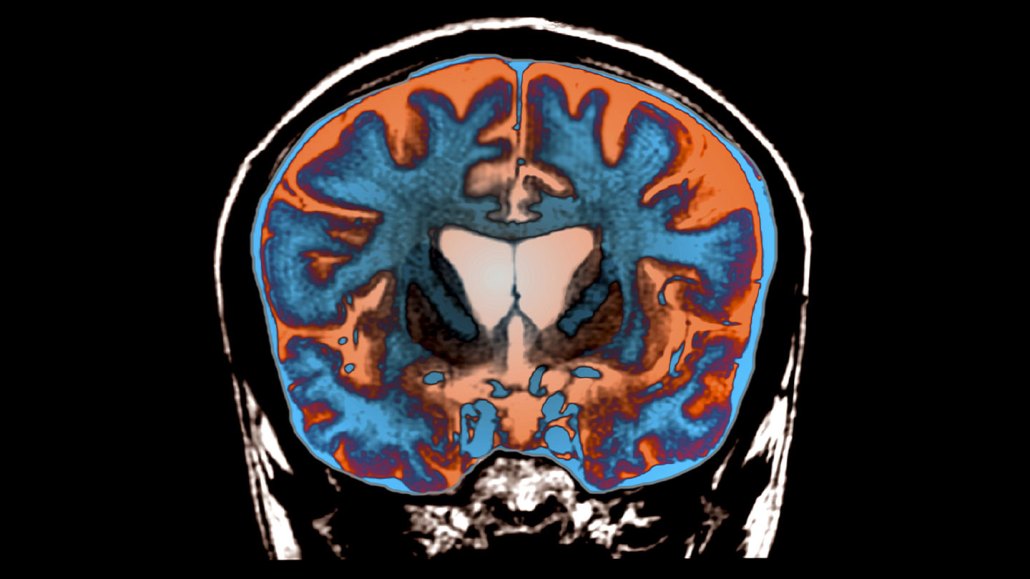

This image shows an MRI scan of the brain of someone with Huntington's disease.

Huntington’s disease causes certain brain regions to die, as indicated by the darker areas in the center of this MRI image of the brain of a 21-year-old with the disease. Researchers have discovered that adding extra DNA to the gene that causes the disease leads to brain cell death.